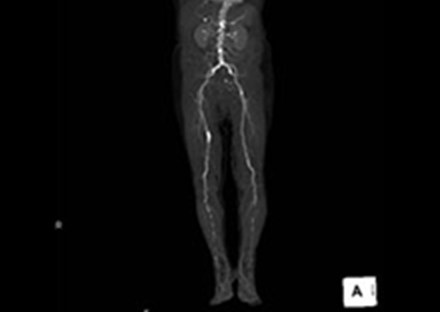

磁力と電波を使った検査でX線被ばく無しで任意の断面の撮影が可能です。脳や脊髄、臓器、腫瘍、関節、軟骨、軟部組織などの撮影に優れており、さらに血流を画像化することができるため、造影剤を使用せずに血管の状態を知ることができます。